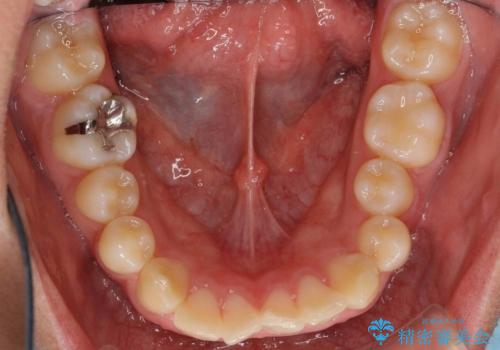

- ワイヤー矯正による治療後7年以上経過した患者様です。当時上の小臼歯を2本抜歯しています。

10代で矯正治療を行い、現在20代になられています。

矯正後8年目になりますが、並びも綺麗に保持でき、また上下の歯がさらにしっかり咬んできているのがわかります。

下は歯につけるタイプのワイヤーを貼っています。